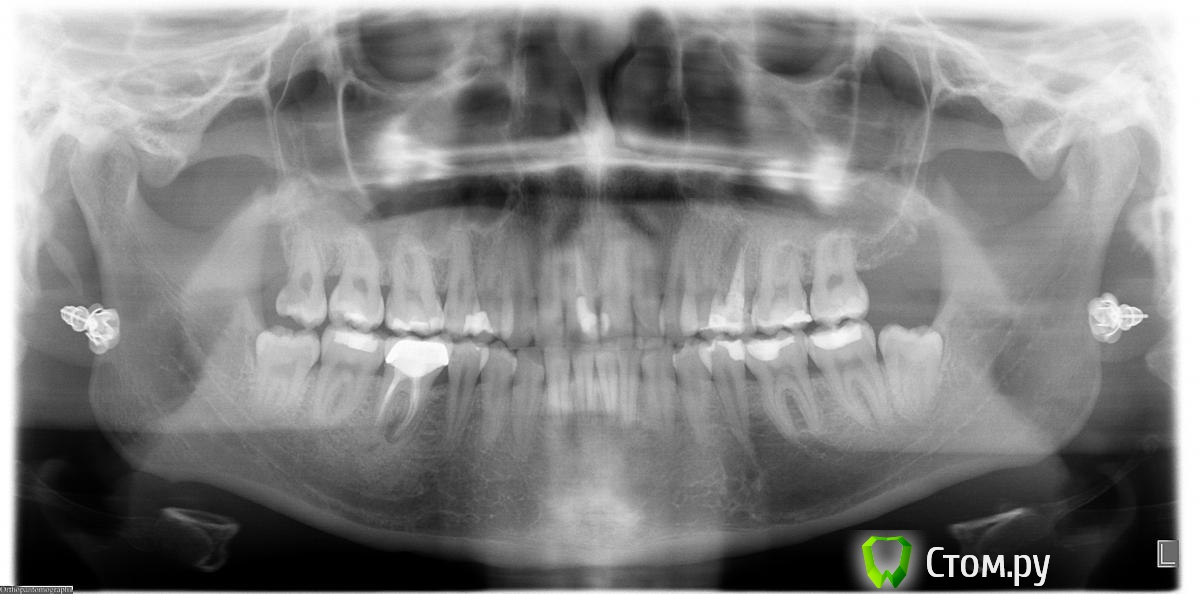

Юлия Арт Опубликовано 13 марта, 2014 Автор Поделиться Опубликовано 13 марта, 2014 вот фото, панорамный сделали сегодня (вторая кист куда-то делась у верхней 5-ки, вырывать зуб не стали),троица с депульпцией болит и ноет сильно, есть на них не могу Ссылка на комментарий

anvladd Опубликовано 13 марта, 2014 Поделиться Опубликовано 13 марта, 2014 17 зуб похоже проблемный уж слишком пломба глубоко. Ссылка на комментарий

Л Ю С Я Опубликовано 13 марта, 2014 Поделиться Опубликовано 13 марта, 2014 1.4 перелечивать, разобраться с 1.7 и 1.5, возможно и 1.6 проблемный Ссылка на комментарий

anvladd Опубликовано 13 марта, 2014 Поделиться Опубликовано 13 марта, 2014 Нерв удалили в 16 а вот 17 судя по снимку под подозрением. И как писала доктор выше 14 перелечивать каналы. Ссылка на комментарий